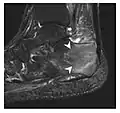

a

b

Figure 10: Calcaneal fatigue fracture in a 30-year-old male runner. Radiographs were normal (not shown). (a) Sagittal T1-weighted and (b) short tau inversion recovery images show a linear hypointensity (arrows) of calcaneal tuberosity within diffuse bone marrow edema, which appears as an ill-defined area of hyperintensity on a fluid sensitive pulse sequence (arrowheads).[1]